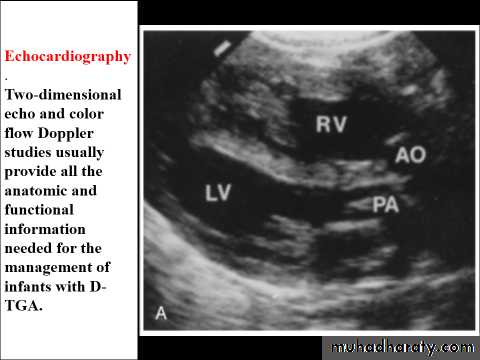

D-Transposition of the Great ArteriesEtiology and Epidemiology

T.G.A represents about 5% of congenital heart defects, and it is the most common cyanotic lesion to present in the Newborn period . T.G.A is ventriculoarterial discordance secondary to abnormalities of septation of the truncus arteriosus, the aorta arises from the right ventricle, anterior and to the right of the pulmonary artery, which arises from the left

ventricle. This transposition results in desaturated blood returning to the right heart and being pumped back out to the body, while well-oxygenated blood returning from the lungs enters the left heart and is pumped back to the lungs. Without mixing of the two circulations, death occurs quickly. Mixing can occur at the atrial (patent foramen ovale/ASD), ventricular (VSD), or great vessel (PDA) level